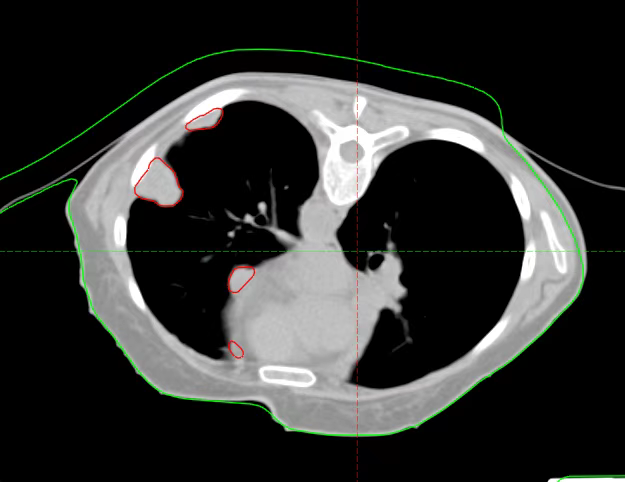

After admission, relevant examinations were completed. After excluding contraindications, radical carbon ion radiotherapy for recurrent thymoma was initiated on January 15, 2025. The radiotherapy doses were as follows: For the part of the left pleura far from the stomach and colon, 72 Gy (RBE)/18 Fx was administered; for the lesions adjacent to the heart border and esophagus, 52 Gy (RBE)/13 Fx was administered; for the part of the left pleura close to the stomach and colon, a basic dose of 40 Gy (RBE)/10 Fx was administered.

Before Radical Regional Treatment